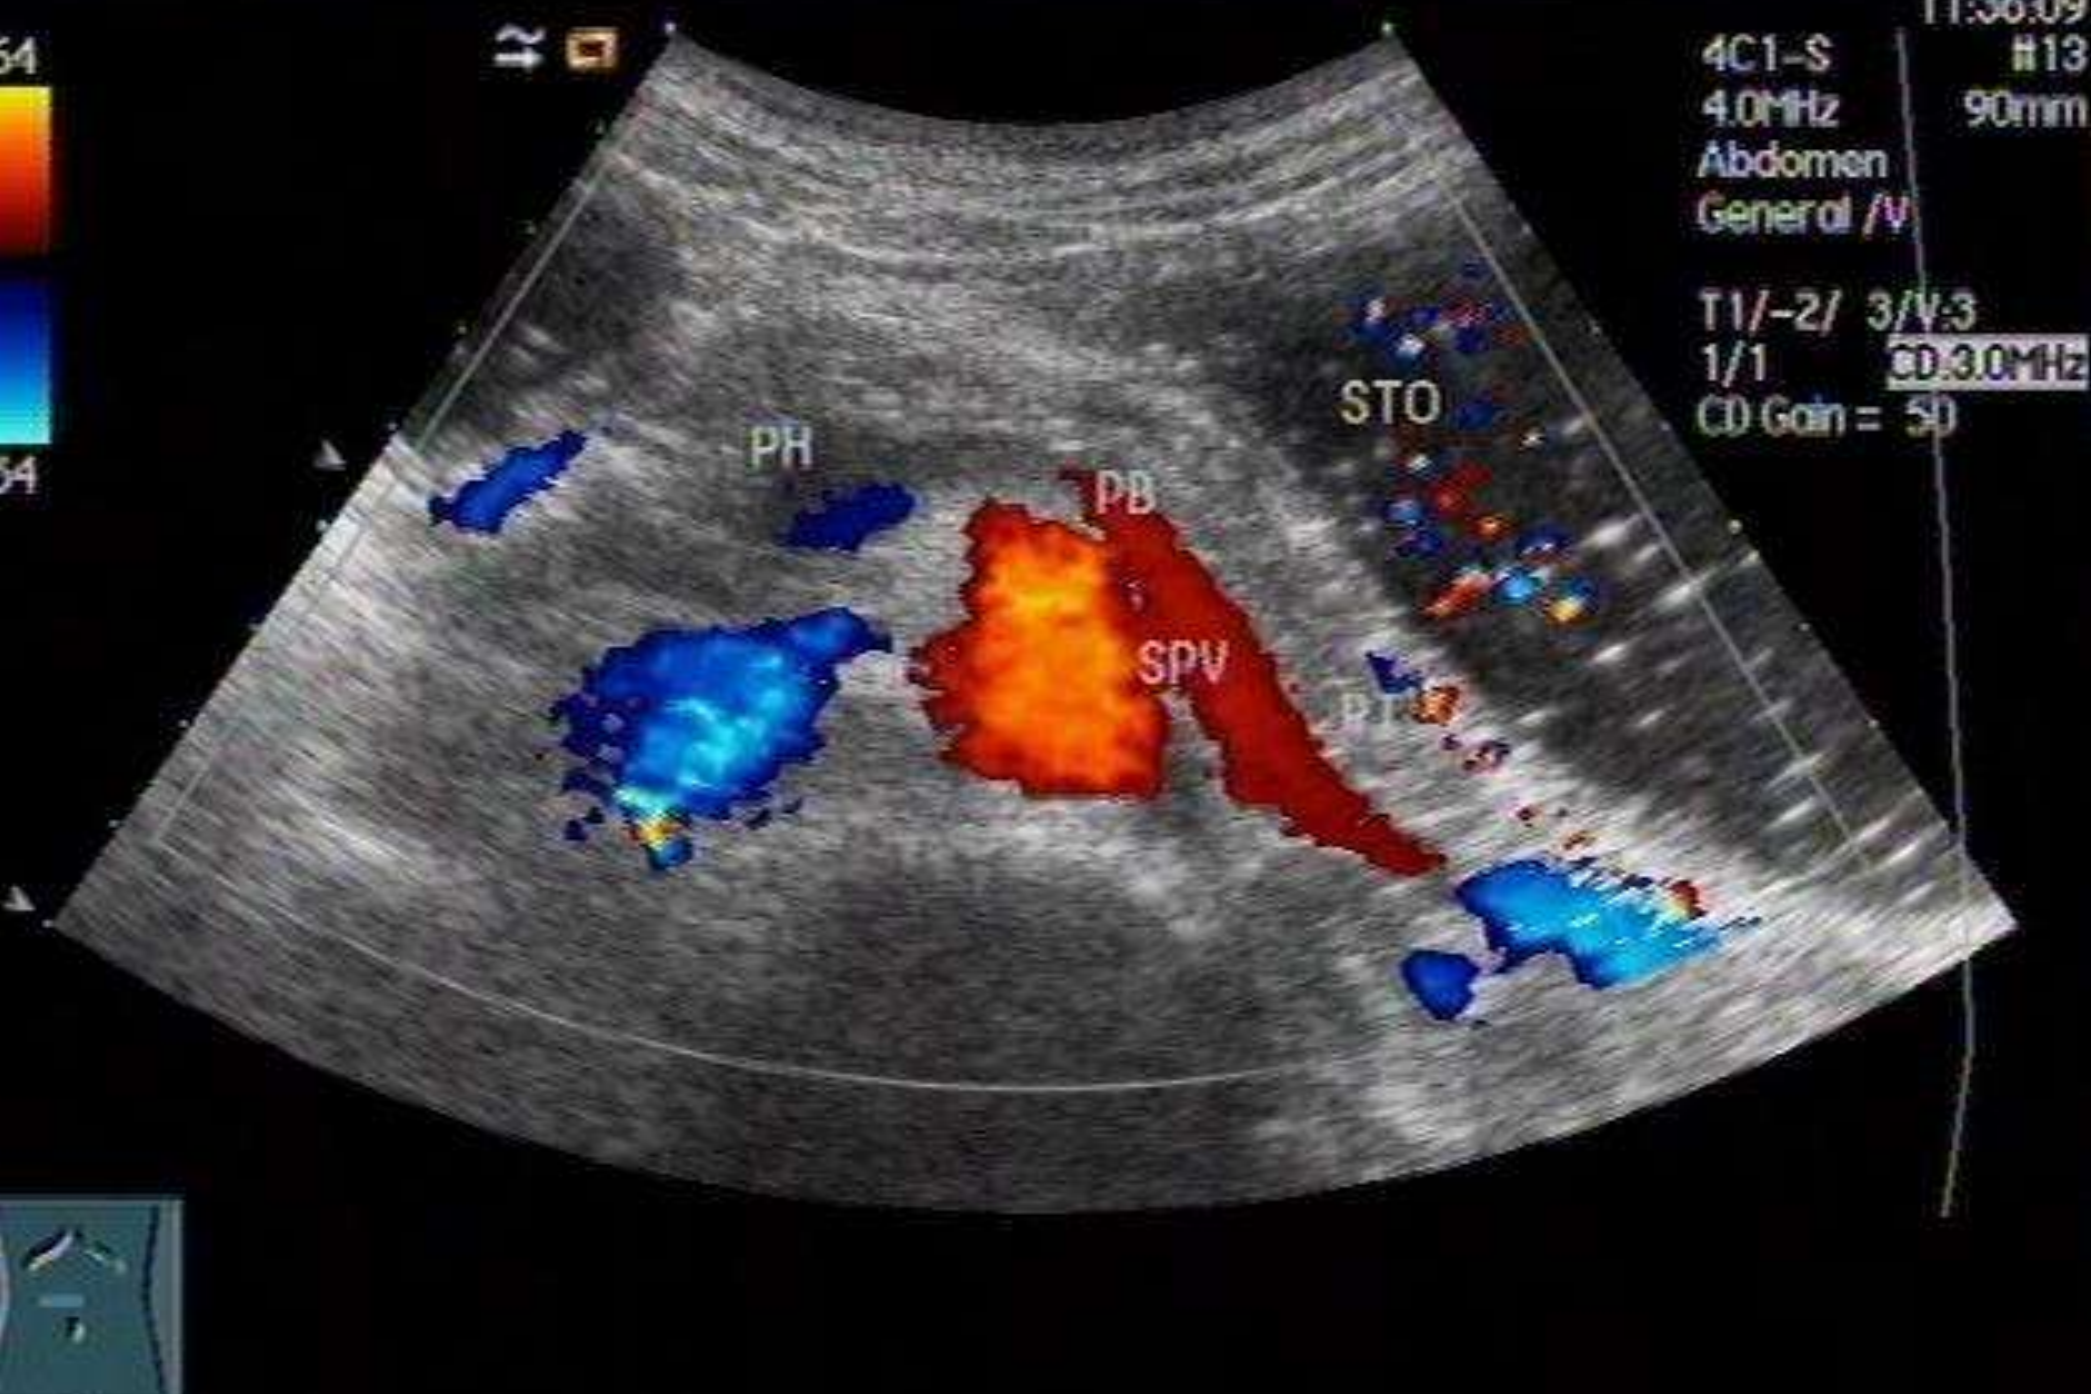

胰腺正常声像图

超声检查时以腹主动脉,下腔静脉,肠系膜上动、静脉和脾静脉等胰周大血管作为识别胰腺的主要标志。胰腺边界光滑而整齐,有时与周围组织间界限不甚清晰。胰头、体、尾前后径的超声测径分别为3cm、2cm及2cm。胰腺实质呈细密的光点回声,多较肝实质回声略强。胰腺中部可见胰主导管通过,其内径一般小于0.2cm。